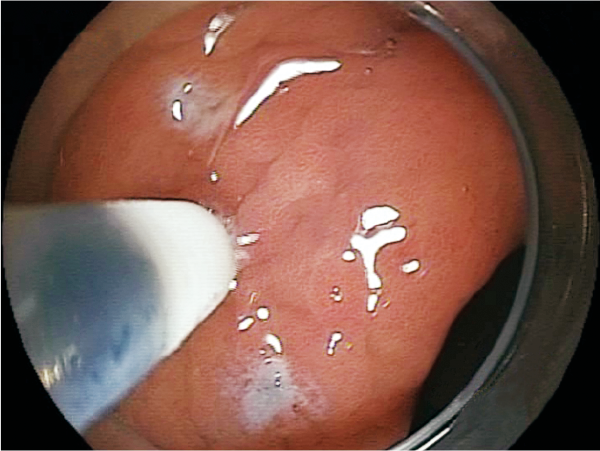

Makes clear marking around the lesion.